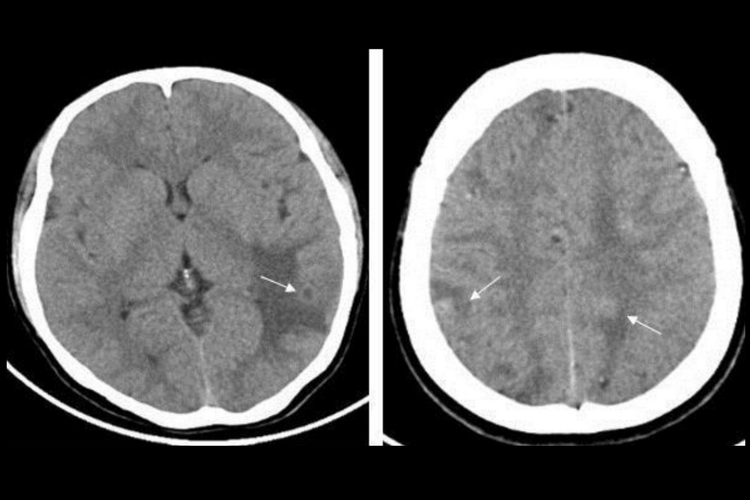

脑囊虫病的患者可出现头痛、癫痫发作、恶心、呕吐,还可出现眩晕、意识障碍、猝倒等颅内压增高的表现,当病灶位于大脑皮层时,可出现相应的运动、感觉、语言障碍,若病灶位于小脑还可能出现共济失调、眼球震颤等症状。病变部位通过CT检查可表现发现低密度影,其内可见小结节状等高密度影,为囊虫头节。